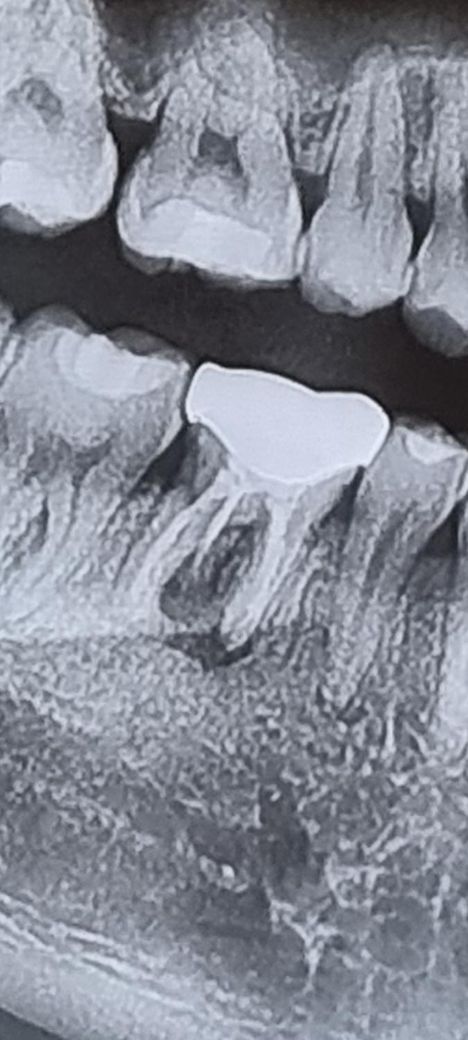

크라운한지 15년이넘었는데 해당치아에 피곤하면 고름이 생겼다 사라지고 반복된게 2년가량된거같습니다 크라운제거후 치아를 열었을때 치료안된뿌리가 있어 치료를 하더라도 이미 만성염증이되어 염증이안사라질거라생각되는데 임플란트를 문의해봐야할까요?

증상이 없으면 관리하시면서 사용하시면되지만 엑스레이 상으로 치아 뿌리끝에 염증이 심한거 같습니다. 발치를 해야될 가능성이 높아 보입니다.

위 사진이 최신 엑스레이 사진일까요?

위 사진상으로도 잇몸뼈가 꽤 녹았습니다. 농양이 만성화되었다면 통증은 없더라도 잇몸뼈가 많이 녹은 상태일 겁니다.

재신경치료를 해도 염증이 잡히지 않을 확률도 있고, 임플란트를 하고자 하더라도 잇몸뼈 상태가 안 좋을 수도 있습니다.